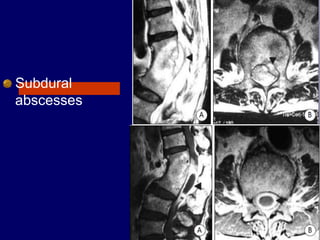

Subdural

abscesses